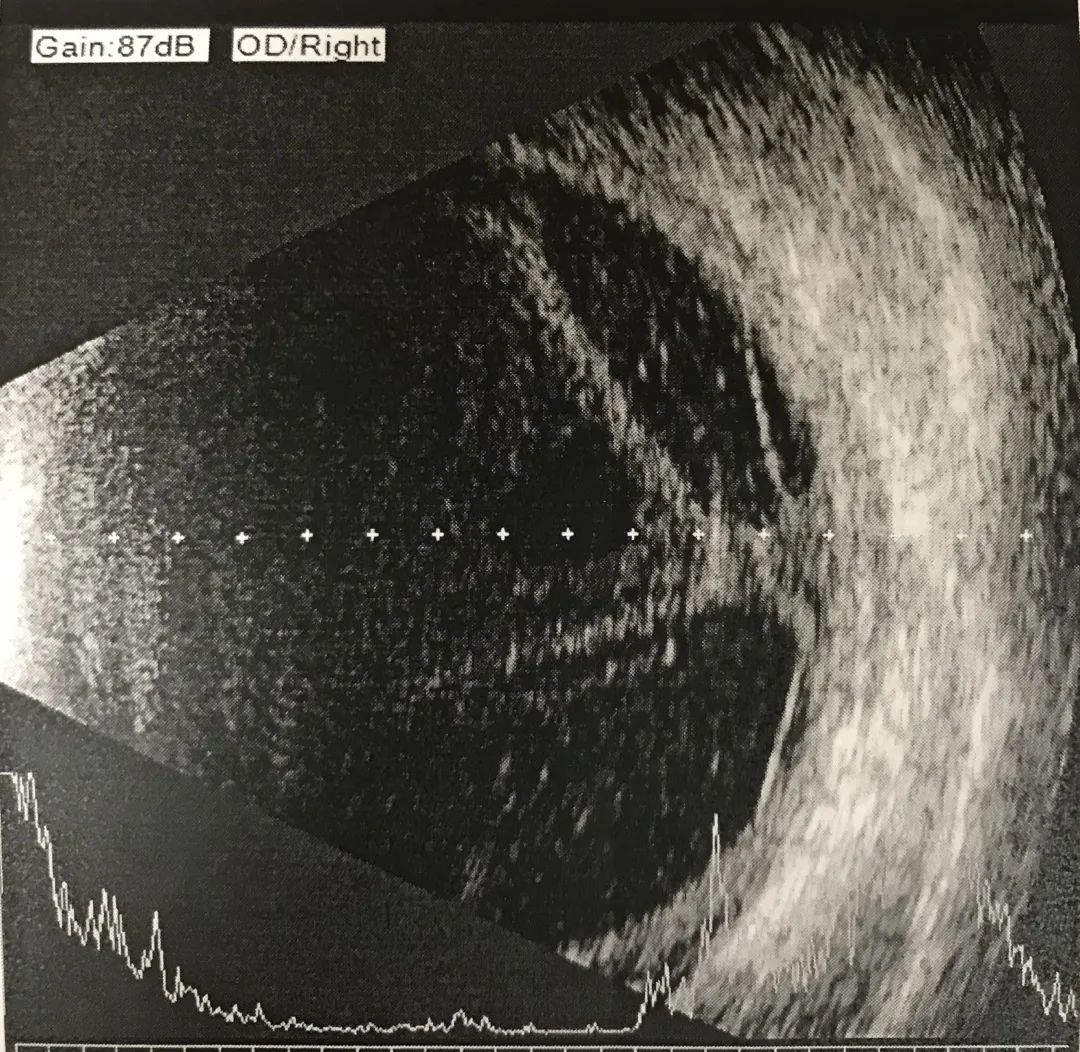

▲眼部B超显示强强右眼玻璃体内存在机化条索,并牵拉视网膜脱离

手术后,通过对强强眼内液的检验,弓蛔虫抗体指标呈强阳性,证实强强确实患上了弓蛔虫眼病 。

“弓蛔虫对眼部会造成巨大损害,很多患儿视力预后较差 ,幸运的是强强右眼的黄斑区还好没有受到太大影响,所以经过后续治疗,应该是可以恢复部分视力的。”盛艳副主任医师说。目前,强强已经出院回家,恢复了正常的上学生活,在最近一次的复查中,他的右眼视力恢复到了0.2(视力表) 。